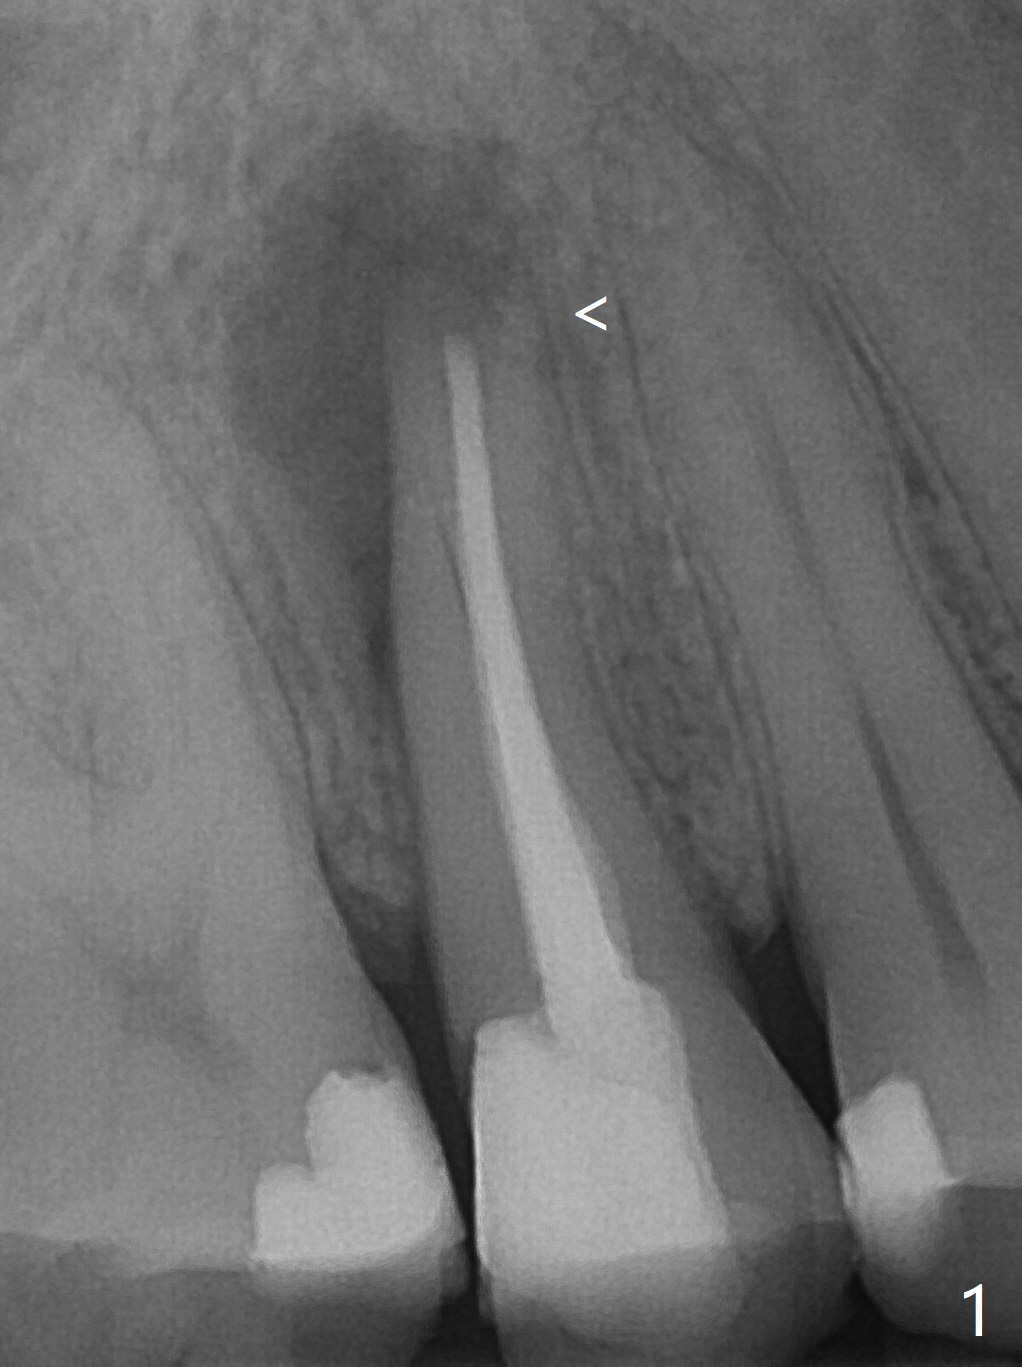

Nine months post apicoectomy of the tooth #4 of a 40-year-old man (Fig.1 <), the root has vertical fracture (Fig.2). It appears that the patient is a bruxer. Place an implant as long as 18 mm (bone level, Fig.3). Start osteotomy in the middle of socket, since there is bone resorption both buccally (apicoectomy) and palately (Fig.4 *). The implant should occupy the meisodistal space for primary stability. Measure root dimension post extraction to determine the implant diameter. Use a 3.8 mm dummy implant.